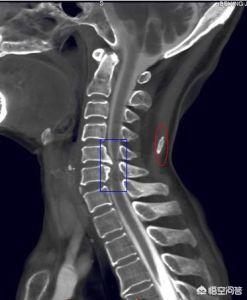

頚椎症は頚椎症とも呼ばれ、退行性病理学的変化に基づく疾患であり、変形性強脊椎症、過形成性頚椎症、頚部神経根症候群、頚椎椎間板ヘルニアの総称である。

第一:退行性変化。時間は殺人ナイフである!頸椎は、最も可動頻度が高く、内部の容積が最も小さいため、変性が最も早い。椎間板内部の水分が徐々に失われ、環状線維が非弾性的になり破裂し、髄核が突出し、椎間腔が狭くなり、鈎シナプスが尖り、変性は通常C5、C6、C7椎骨で最も顕著である。

頚椎症に対する理解は、ここ数十年の問題である。頚椎症の根本的な原因は、頚椎椎間板の退行性変化、椎間体のゆるみ、椎骨の縁に骨棘ができることであると現在では認識されている。)、または椎間板の破裂や脱出、神経根、脊髄、椎骨動脈の圧迫によるその他の症状。

椎間板は、内側の髄核と外側の環状線維体から構成されており、正常な椎間板は、髄核に80%、環状線維体に65%の水分を含んでいるが、加齢とともに水分量は徐々に減少し、弾力性や靭性が徐々に失われていく。もちろん、椎間板が破裂したり、脱出したりすると、水分を含む量が少なくなり、椎間板が弱くなって体重を支える役割を失い、椎間腔が狭くなり、頸椎が曲がるときに椎体が前後に正しく動かず、椎間不安定性が生じる。

椎骨棘

椎間板が変性すると、椎間板が弱くなり、椎間腔が狭くなり、椎体が不安定になり、ずれが生じ、この活動によって線維性環状骨と周囲の縦靭帯が引っ張られ、さらに椎体の端が引っ張られ、骨膜下出血を引き起こし、血腫が機械化骨化し、骨棘ができる。

骨棘のような硬いヘルニアが頚椎症の一般的な原因であることを示した研究もある。このような骨棘は、周囲の神経根、脊髄、椎骨動脈を圧迫し、頚椎症の臨床症状を引き起こします。